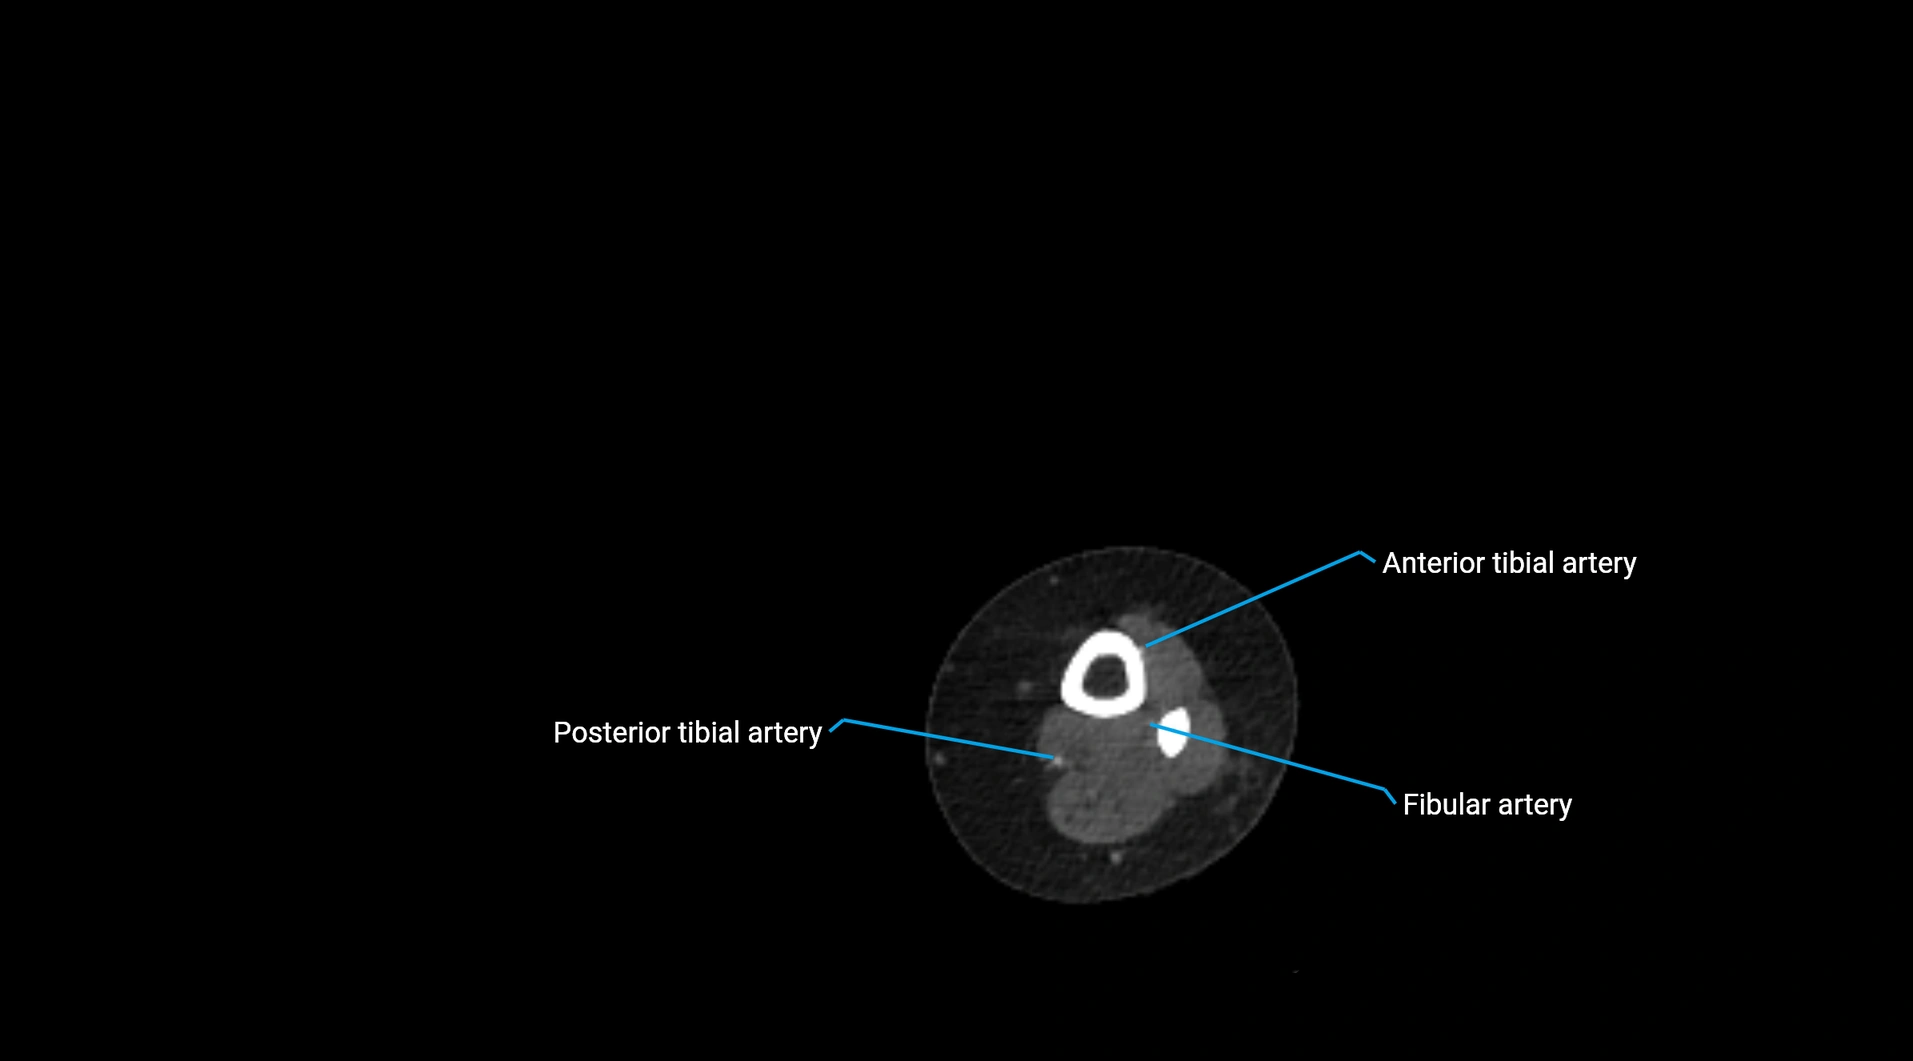

CT Appearance

Non-contrast CT:

• Appears as a tubular soft tissue structure anterior to vertebral bodies

• Calcified atherosclerotic plaques appear as hyperdense foci along the wall

• Useful for screening abdominal aortic aneurysm (AAA) size and mural calcification

Contrast-enhanced CT (CTA):

• Gold standard for abdominal aortic imaging

• Provides excellent detail of lumen, wall, aneurysm, thrombus, and branch vessels

• Multiplanar and 3D reconstructions help in aneurysm measurement, stent graft planning, and dissection evaluation

• Detects acute rupture, traumatic injury, or occlusion with high sensitivity